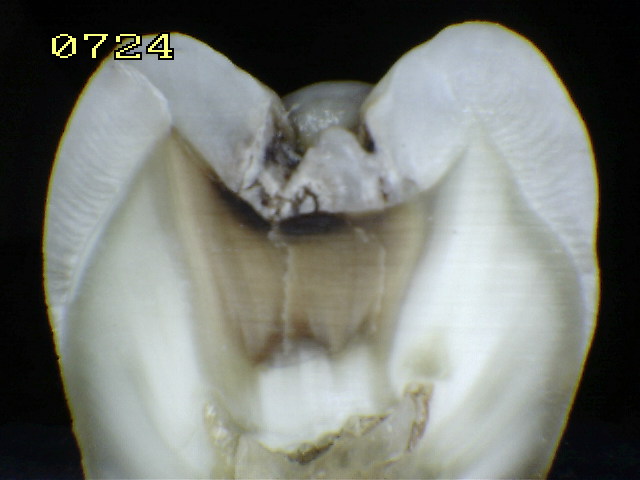

Espécimen Nº 12

Lesión característica de un código 4

Esquema del corte sagital

Se verifica un código 3 histológico

Observe en el corte sagital la vitalidad pulpar, debido a que las fotografías y el corte se hicieron a unas pocas horas de la exodoncia, conservando así la humedad natural del diente.